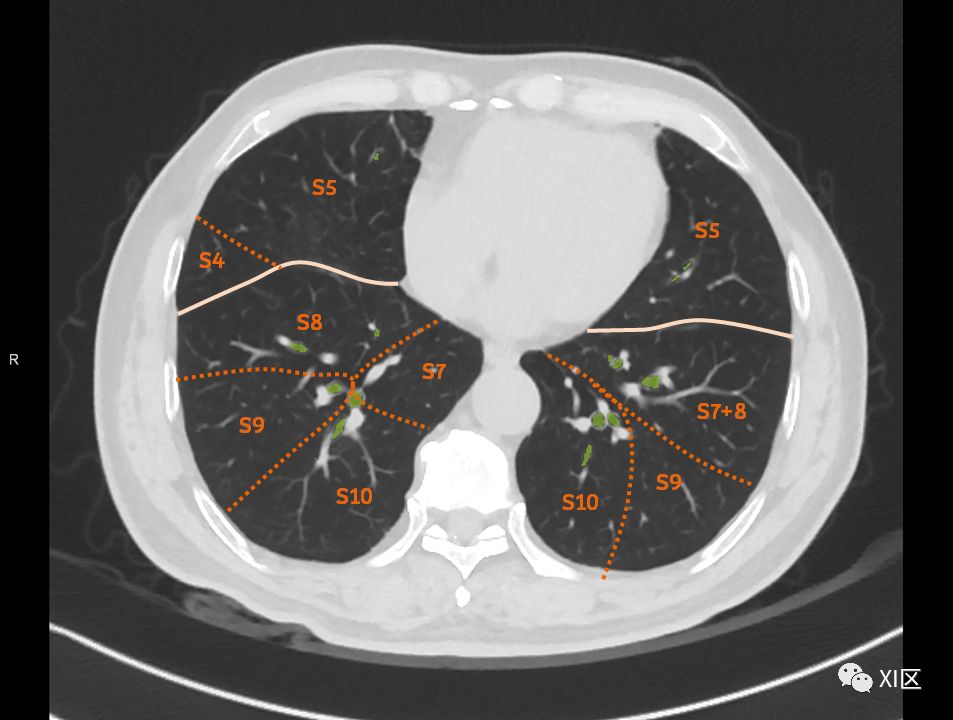

肺的断层分段示意图

在进行肺的分段时,可以上下观察浏览,沿着相应气管的走形可以更容易准确地进行分段。